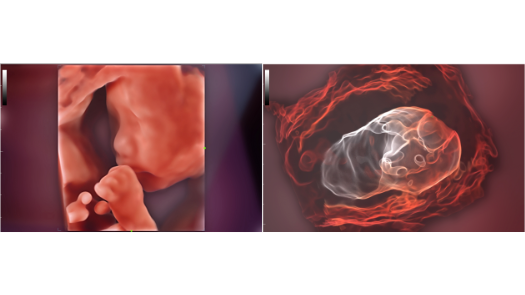

Stworzona specjalnie dla U?ytkownikÃģw z zakresu podstawowej opieki zdrowotnej, Consona wykorzystuje nowe rozwi?zania, ktÃģre efektywnie pomog? wykona? bez problemu diagnostyk? u rÃģ?nych pacjentÃģw.

Bez wzgl?du na to, czy pracujesz w szpitalu, przychodni, czy u?ywasz ultrasonografu do badaÅ ogÃģlnych, w opiece zdrowotnej kobiet lub w badaniach sercowo-naczyniowych, w serii Consona znajdziesz bardzo pot??ne narz?dzia, aby utrzyma? si? w czo?Ãģwce.